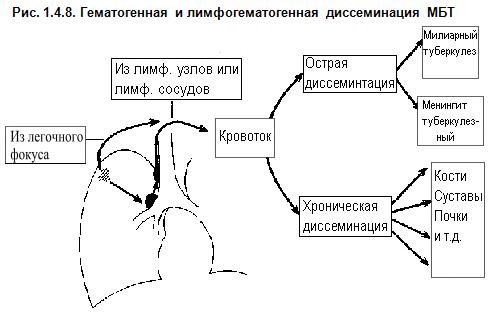

В клинической картине острого гематогенно диссеминированного туберкулеза преобладает